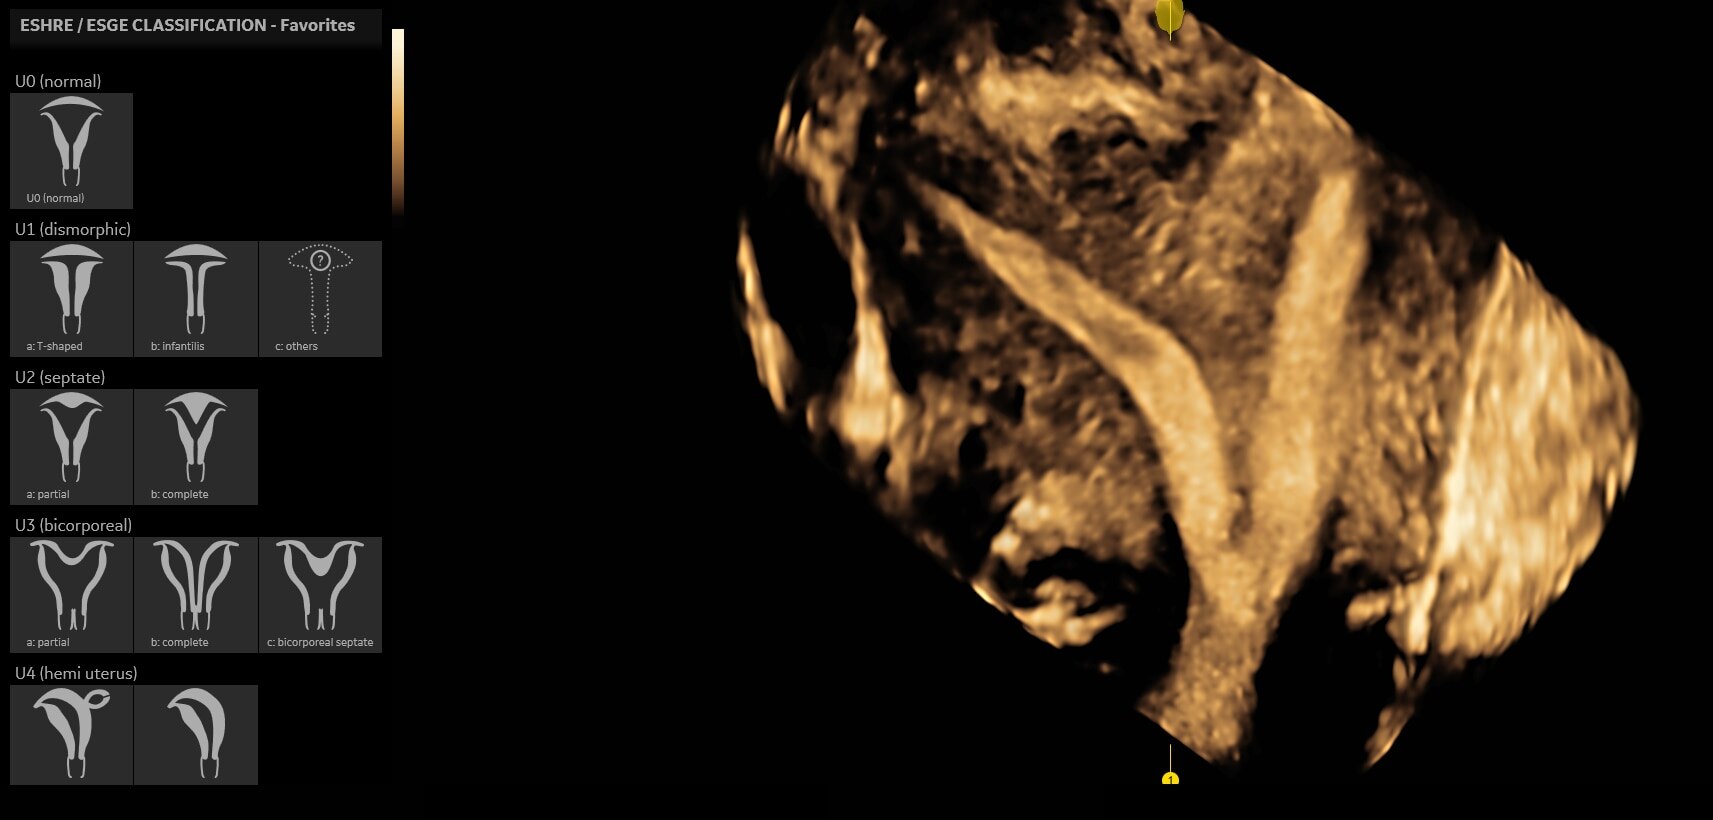

• Uterine Trace acquires the volume and then displays the coronal view of the uterus linking to ASRM, ESHRE and ESGE Uterine Classification guidelines to simplify identification and reporting of uterine malformations